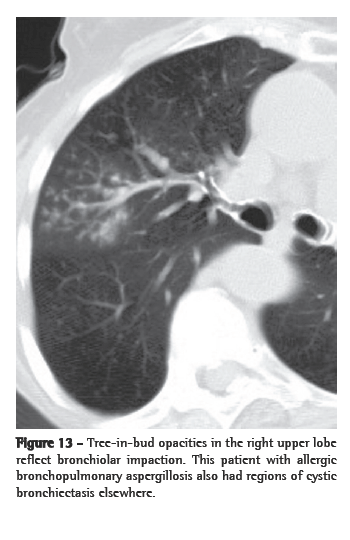

Centrilobular nodules

The central part of the secondary pulmonary lobule contains the branches of the terminal bronchioles, their accompanying pulmonary arteries, and, adjacent to them, supporting connective tissue with lymph vessels. Therefore, centrilobular nodular opacities can result from bronchiolar and peribronchiolar diseases, as well as from vascular and perivascular diseases. Mosaic attenuation associated with air trapping on expiratory HRCT, or functional evidence of airflow obstruction indicates diseases involving the peripheral airways. Centrilobular nodules are sometimes accompanied by the so-called "tree-in-bud" opacities, in which the abnormality resembles a budding tree. In the majority of cases, the tree-in-bud pattern occurs as a result of infectious diseases. Tree-in-bud is a subtype of a centrilobular pattern. Pathologically, this abnormality represents bronchiolar impaction and is almost always due to infection. The differential diagnosis is detailed in Chart 7.

In the immunocompromised host, bacterial (Staphylococcus aureus and

Haemophilus influenzae), fungal (more commonly Aspergillus spp.) and, quite rarely, viral infection can all result in a tree-in-bud pattern (Figure 13) accompanied by variable consolidation (including cytomegalovirus and respiratory syncytial virus).(55)